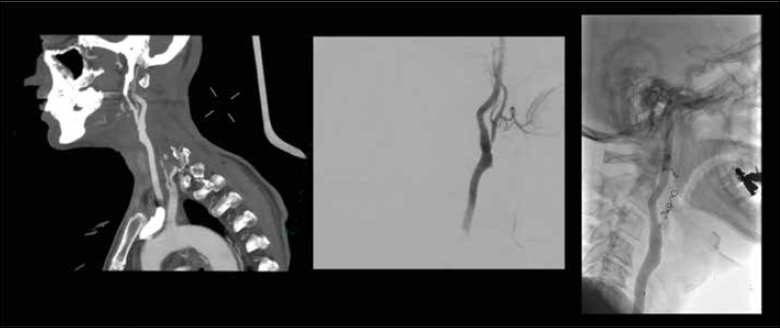

Neurovascular intervention was the preferred treatment in 92% (n = 47) of events. Among the 67% (n = 34) treated with an embolisation procedure, 26% (n = 13) included insertion of a stent for revascularization. Figures 1 and 2 describe two specific occurrences of an imminent carotid blowout and the neurovascular intervention adopted.

Figure 1. A sagittal CT angiography of a 62-year-old male with advanced laryngeal SCC post-CRT showed a pseudoaneurysm in the left common carotid artery near the stoma site. The image highlights the coil embolisation targeting the left ECA to mitigate the risk of rupture.